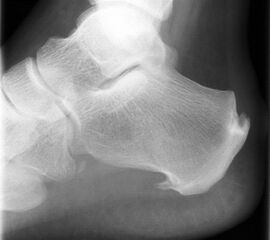

Die Plantarfasziitis ist eine degenerative Erkrankung des Ursprungs der Plantaraponeurose am Tuber calcanei. Das Vorhandsein eines knöchernen Fersenspornes beschreibt dabei zunächst eine radiologisch sichtbare Veränderung, ist aber nicht zwingend mit einer Plantarfasziitis verknüpft 1920.

Ein Röntgenbild der Ferse seitlich ist zum Ausschluss knöcherner Pathologien hilfreich.

In Abhängigkeit des gesamten klinischen Bildes und der Vorgeschichte kann ein MRT z.B. zum Ausschluss einer Stressfraktur oder Ruptur der Plantarfaszie erforderlich werden. Es hat sich bewährt, in Fällen eines mehrmonatigen Krankheitsverlaufes und sonographisch verdickter Plantarfaszie >8mm (Normwert <4mm) vor Therapiebeginn ein MRT zum Ausschluss von Teilrupturen durchzuführen. Obwohl auch in diesen Fällen eine Stoßwellentherapie erfolgen kann, ist eine derartige Information aus juristischen Gründen von Bedeutung.